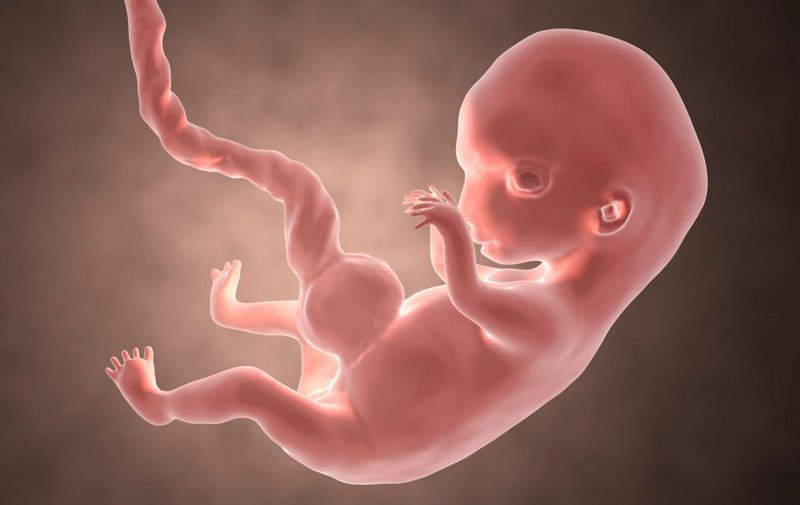

Bào thai là giai đoạn phát triển của thai nhi từ khi phôi được thụ tinh đến khi sinh ra. Trong quá trình phát triển, hệ thống tuần hoàn của bào thai đóng vai trò rất quan trọng để cung cấp dinh dưỡng và oxy cho sự phát triển của thai nhi. Dưới đây là các yếu tố cụ thể về hệ thống tuần hoàn của bào thai:

- Lồng ngực và tim thai: Lồng ngực của bào thai chứa tim thai, một cơ quan quan trọng trong hệ thống tuần hoàn của bào thai. Tim thai bắt đầu phát triển từ tuần thứ ba của thai kỳ và hoàn thiện vào khoảng tuần thứ tư. Tim thai có 4 buồng và hoạt động giống như tim người lớn, bơm máu đưa oxy và dinh dưỡng đến các bộ phận của cơ thể thai nhi.

- Mạch máu thai: Mạch máu thai là mạch máu lớn nhất trong hệ thống tuần hoàn của bào thai. Nó bắt đầu phát triển từ tuần thứ tư của thai kỳ và hoàn thiện vào khoảng tuần thứ tám. Mạch máu thai đưa máu giàu oxy và dinh dưỡng từ lồng ngực của bào thai đến các bộ phận của cơ thể thai nhi. Sau đó, máu trở lại tim thai thông qua các tĩnh mạch.

- Mạch máu rốn: Mạch máu rốn là mạch máu lớn nhất trong hệ thống tuần hoàn của bào thai. Nó bắt đầu phát triển từ tuần thứ năm của thai kỳ và hoàn thiện vào khoảng tuần thứ mười hai. Mạch máu rốn đưa máu giàu dinh dưỡng và oxy từ dạ dày của mẹ đến bào thai. Sau đó, máu trở lại mạch máu rốn thông qua các tĩnh mạch.

- Mạch máu tâm thất: Mạch máu tâm thất là mạch máu nhỏ nhất trong hệ thống tuần hoàn của bào thai. Nó đưa máu giàu oxy và dinh dưỡng đến các bộ phận của cơ thể thai nhi thông qua các mạch máu nhỏ hơn. Sau đó, máu trở lại tim thai thông qua các tĩnh mạch.

Từ khi một quả trứng được thụ tinh bởi tinh trùng, quá trình phát triển của một bào thai trong tử cung là một quá trình phức tạp và kỳ diệu. Trong quá trình này, tuần hoàn bào thai trải qua nhiều giai đoạn và thay đổi để phát triển từ một tế bào đơn lẻ thành một cơ thể hoàn chỉnh. Dưới đây là một tóm tắt về sự phát triển của tuần hoàn bào thai:

- Phát triển các bộ phận bên ngoài: Trong giai đoạn này, các bộ phận bên ngoài của tuần hoàn bào thai bắt đầu hình thành. Các bộ phận như tay, chân, mắt và tai bắt đầu phát triển và hình dạng của chúng trở nên rõ ràng.